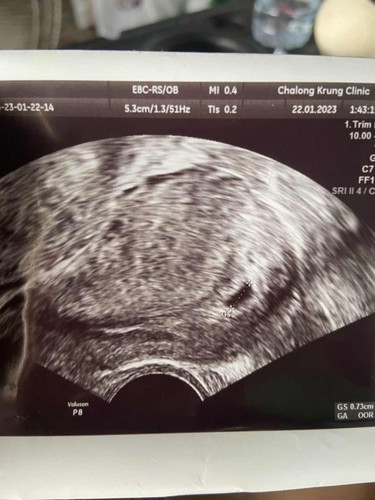

อายุครรรภ์4สัปดาห์6วันเจอถุงการตั้งครรภ์ไม่เจอตัวเด็ปกติไหมคะ

ถุงการตั้งครรภ์0.73cm.ค่ะ